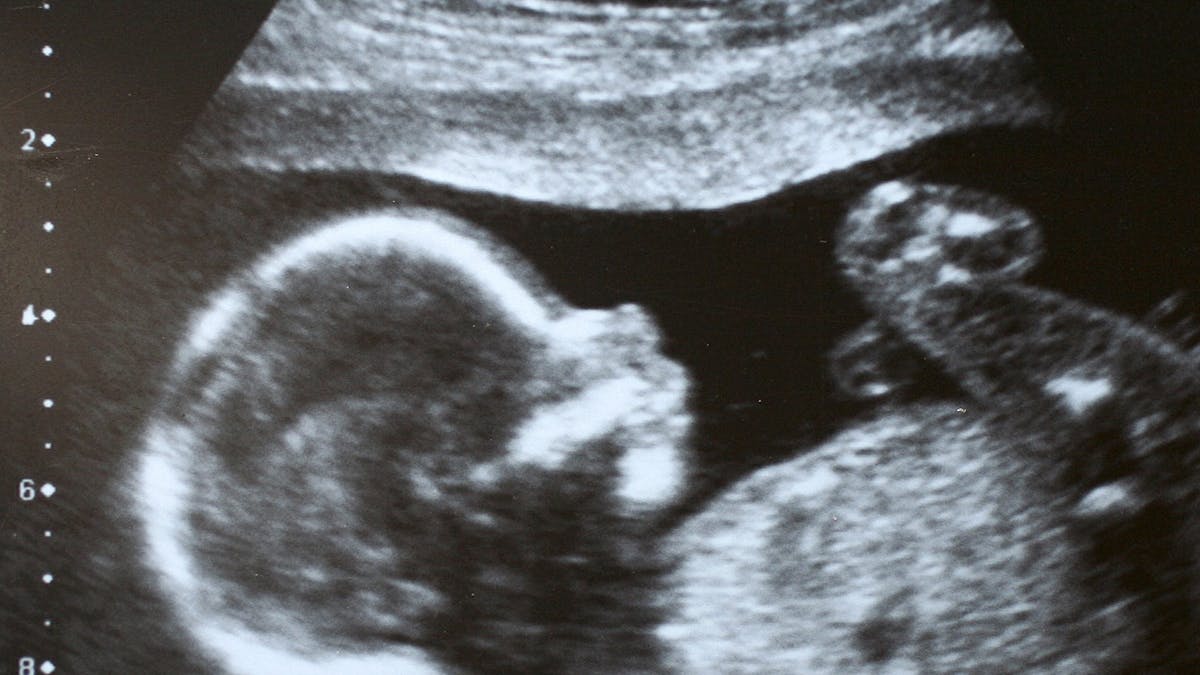

A 6 semaines de grossesse, je suis partie chez la gynéco parque j'avais un retard et de fortes douleurs au bas du ventre au niveau de l'ovaire gauche Elle m'a fait une échographie vaginale, mais ce qui m'inquiète c'est que la gynécologue m'a dit que l'embryon était trop petit 3,9 mm, le sac est de 10,7 mm J'ai vu son cœur qui bat mais elle a dit qu'il est bien en place Vous êtes enceinte de 6 mois et vous faites désormais votre entrée dans le dernier trimestre de grossesse S'il ne vous reste plus beaucoup à patienter avant de rencontrer bébé, ces quelques mois restants vont permettre à votre toutpetit de se faire une beautéEn effet, j'ai eu ma visite des 6 mois aujourd'hui et je souhaitais faire un petit bilan avec vous comme je souhaite le faire dans les trois derniers mois qui vont suivre !

Durant le sixième mois de grossesse, votre ventre s'arrondit et bébé grossit Votre fruit est visible et, d'ailleurs, vous commencez à en sentir le poids sur votre dos, sur vos vertèbres et vos jambes Doctissimo vous présente les changements qui accompagnent ce 6e mois de grossesse pour vous et pour votre bébé, ainsi que les examens et les conseils indispensablesIl vous réveille lorsqu'il s'agite, réagit à vos caresses, vous écoute Au sixième mois de grossesse, plus de Mon bébé estil trop grand ?